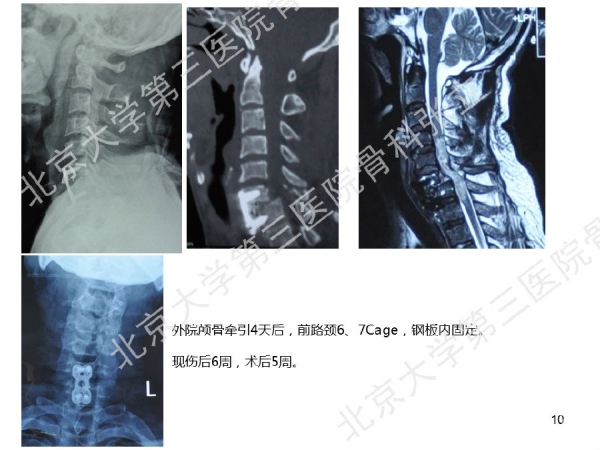

徒手置钉的下颈椎椎弓根钉技术对于很多骨科同道来说,无疑是难度超高、不敢触及的一项技术。已熟练掌握这一技术的北京大学第三医院骨科张立主任医师认为,下颈椎椎弓根钉徒手置钉技术固定可靠,能满足绝大多数后路固定所需,可应用于脊柱外伤、脊柱畸形、脊柱肿瘤,以及CSM伴退变性颈椎后凸畸形。它的优势是:螺钉尾部靠外,不影响椎板成形术;先置钉固定,后开门,更安全;和椎板成形术完美结合,减压、复位、固定一次完成;极少出现脊髓、神经根及椎动脉损伤。